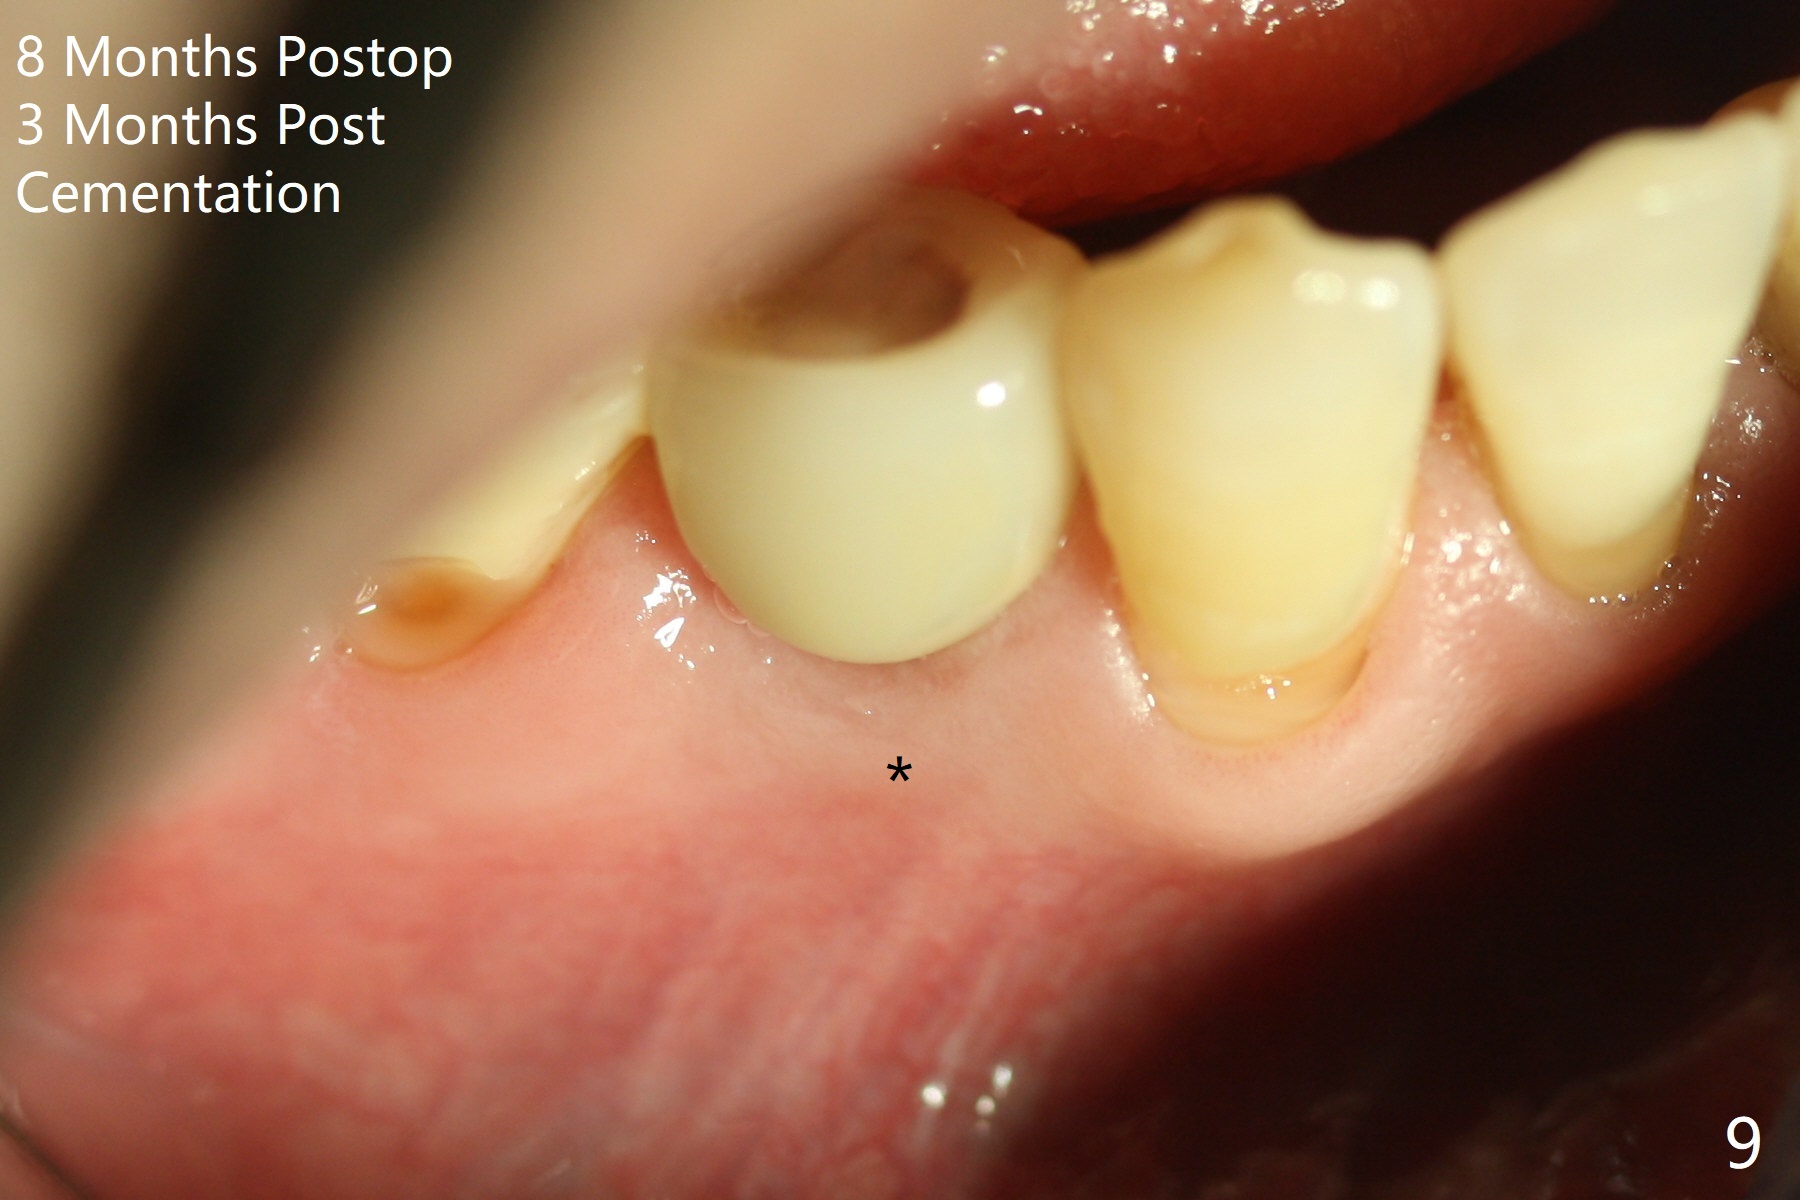

Immediately post extraction and curettage of the large buccal apical lesion, osteotomy is established in the lingual wall of the socket of #28 (slightly distal) for 17 mm vs. 15 mm socket depth (Fig.1 (red line: Mental Loop)). Following sequential osteotomy until 3.5x17 mm drill, a 4x10 mm dummy implant is partially placed with stability (Fig.2,3 (root measurement: mesiodistal 4 mm; buccolingual 7 mm)). A final implant (4x11.5 mm) is placed with insertion torque of 60 Ncm (Fig.4,5). Since the buccal crest is lower with the buccal gingival recession, the implant is intentionally placed deep as well as lingually so that autogenous bone and Vera graft mixture will be placed in the buccal gap (Fig.6 * (gauze at the moment)). The apical lesion decreases 4.5 months postop (Fig.7). Immediate implant and immediate provisional keep the papillae (Fig.8 *), but cannot prevent the buccal plate from atrophy (Fig.9 *). It appears that socket shield is able to accomplish the latter. The bone density next to the coronal threads increases 10 months post cementation (Fig.10 *) and seems to have continued to do so 1 year 4 months post cementation (Fig.11).